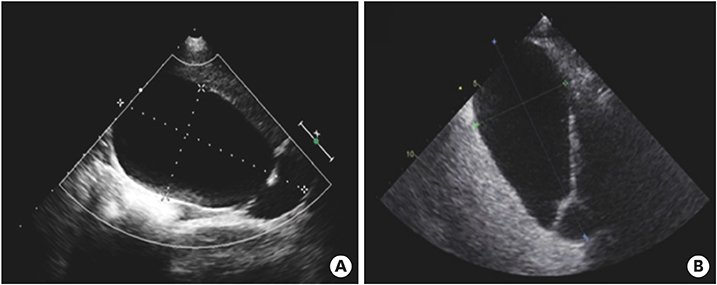

After discharge and 23 days of fever onset, a follow-up abdominal sonography revealed a slower regression of the GB hydrops (Fig. 5A). Echocardiography performed at 81 days after onset of fever revealed complete improvement of both the coronary artery lesion and GB hydrops (Fig. 5B).

Fig. 5

Abdominal ultrasonography (A) performed at 23 days after fever onset revealed a slow regression of the gallbladder hydrops (6.7×3.2 cm in size). Echocardiography (B) performed at 81 days after fever onset revealed a complete improvement in gallbladder hydrops and a normal gallbladder.